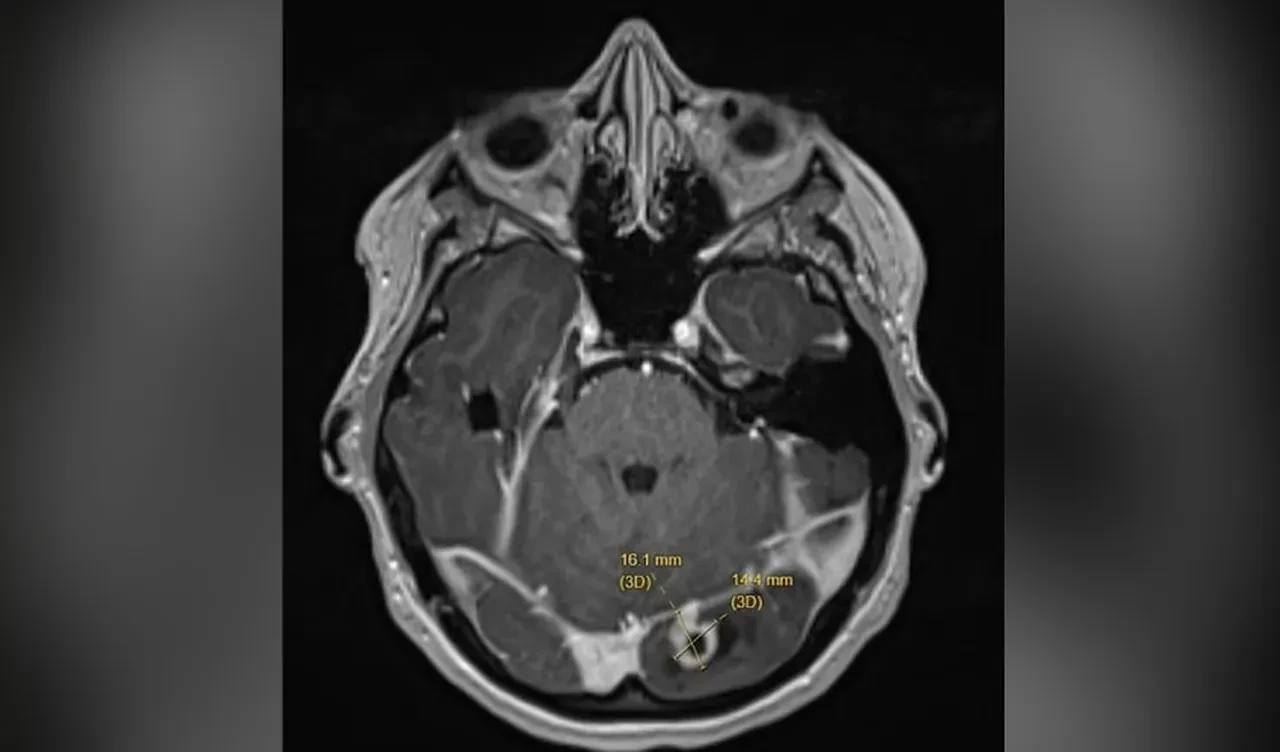

Acil olarak hastaneye kaldırılan Ash'e beyin tümörü teşhisi konuldu. Tümör, Ash'in sol oksipital lobunda bulunuyordu. Kanserli olmayan hücre, hamilelikte hormonel değişimlerin tümörü tetikleyerek nöbet başlatmış olabileceği düşünülüyor.